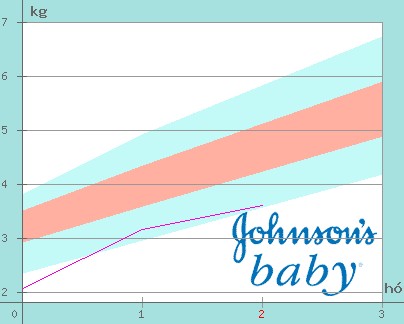

Nálunk Emese:4280gr,Adél:3960gr.Érdekes,hogy születésük óta tartják a 300 gr körüli különbséget.